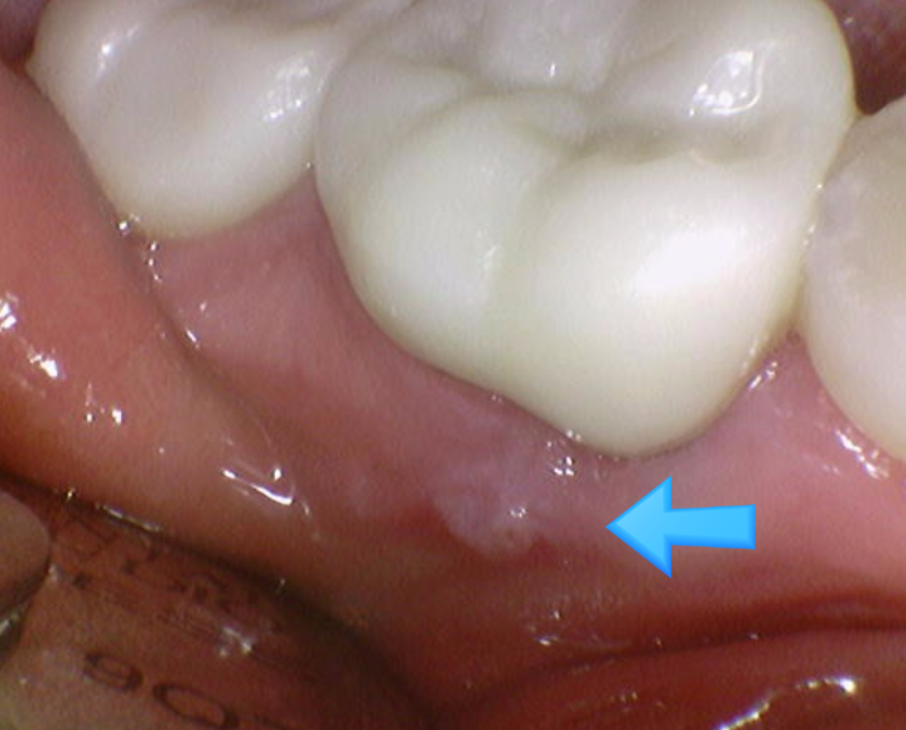

문제의 치아는 발치 후

염증을 깨끗하게 제거해주었습니다.

임플란트 식립 한 시간보다

염증 제거한 시간이 길 정도로

최대한 고름을 긁어내고

깨끗하게 만들어주었습니다.

염증이 남아있으면 임플란트에도 좋지 않기 때문이죠~

뼈와 잘 붙지 않고

문제를 일으킬 수 있어요

240208

염증이 있던 부위라

임플란트 골유착이 잘될 때까지 충분히 기다려주었습니다.

ct 상에서 임플란트 주변으로 잇몸뼈가 잘 찬 것을 확인후

머리를 만들어 주었어요